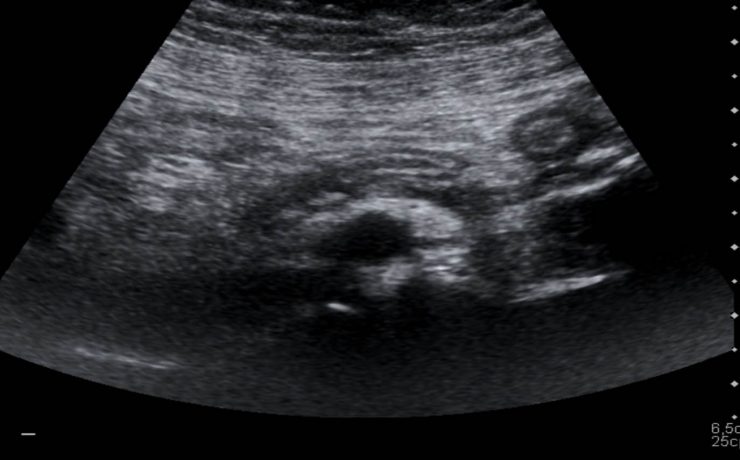

Alteraciones segundo trimestre de gestación.

Objetivo determinar la asociación entre ausencia e hipoplasia del hueso nasal fetal y alteraciones estructurales y/ o cromosómicas en el neonato, en la población en general en el ultrasonido del segundo trimestre. La gran mayoría de malformaciones congénitas no son prevenibles ya que constituyen accidentes en la organogénesis embrionaria y